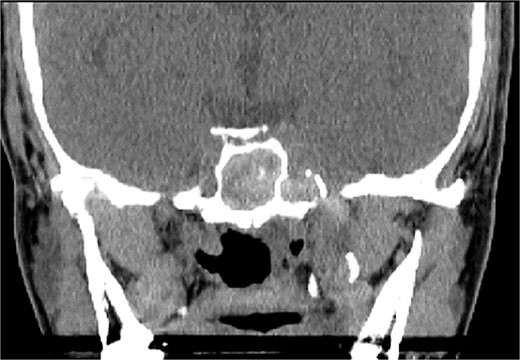

A 36 years-old man with no previous history of medical disease presented to the otolaryngology clinic with a chief complaint of headache that was associated with pressure feeling mainly in the occipital area. He also reported a post-nasal drip. The patient underwent a non-contrast paranasal sinus CT scan (Fig. 1) that demonstrated an isolated sphenoid sinus homogenous opacification, most likely representing sphenoid fungal ball. A decision was made to proceed with endoscopic sphenoidotomy (Fig. 2) to clean and remove the debris, which confirmed the diagnosis of sphenoid sinus fungal ball.

Intra-operative (A and B) endoscopic sphenoidotomy showing fungal debris, with post-operative examination (C) showing clean wide sphenoid sinus free from fungal debris.

An asthmatic 42-years-old patient who was previously medically treated for allergic rhinitis with no significant improvement. A subsequent CT scan revealed isolated sphenoid sinus disease (Fig. 3). Intra-operative endoscopic findings revealed fungal mud and mucin (Fig. 4A and B) with post-operative (Fig. 4C) endoscopic finding of widely open, clean sphenoid sinus. Further histological examination of the specimen proved the diagnosis of eosinophilic AFS.

Coronal CT scan image showing complete sphenoid sinus heterogenous opacification.

Intra-operative (a, b, and c) endoscopic sphenoidotomy showing mud and mucin, with post-operative examination (d) of right optico-carotid recess showing wide and clean sphenoid sinus.